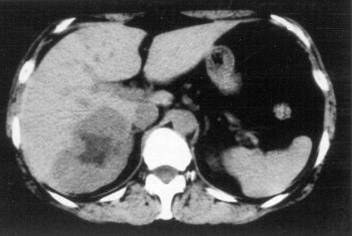

Concerning the HCC, the knowledge of history is very important for the decision and usually the oncoteams consider the performance of an imaging modality guided biopsy basically important for the further therapeutic decisions (because of the hystological validation rather core biopsy should be performed! (Figure 26, 27, 28).

Figure 26: HCC, verified with FNAB, US

Figure 27: HCC, TAE, agniography

Figure 28: HCC, native CT after TAE